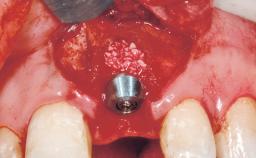

Late Placement of an Implant in a Maxillary Left Central Incisor Site

Bone Augmentation Horizontal|Staged

Augmentation Materials Xenogenous|Membrane

Soft Tissue Grafting Simultaneous

Bone Volume Deficient horizontally, requiring prior grafting